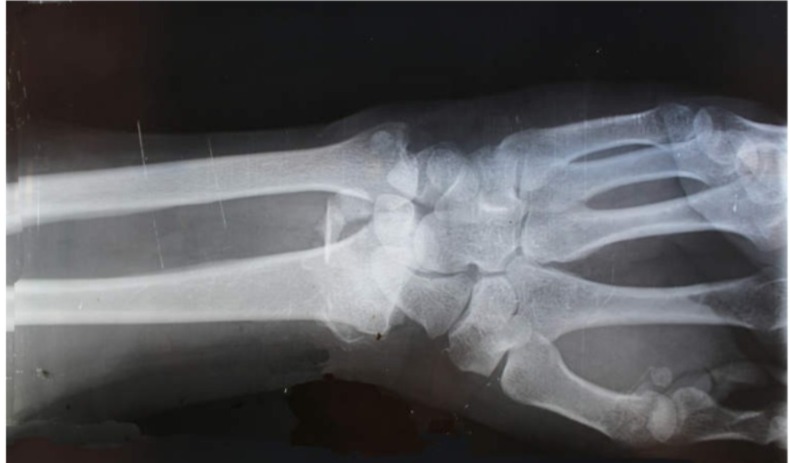

BEIJING: Sekumpulan penyelidik di China mendakwa berjaya membangunkan satu inovasi revolusioner berbentuk ‘super glue’ tulang yang mampu memperbaiki patah tulang hanya dalam beberapa minit, berbanding tempoh berbulan-bulan yang diperlukan secara tradisional. Produk yang dinamakan Bone-02 ini dibangunkan oleh penyelidik Universiti Zhejiang, Hangzhou, telah digunakan serta berjaya dalam lebih 150 kes percubaan. Menurut pakar ortopedik Hospital Sir Run Run Shaw, Dr. Lin Xianfeng, Bone-02 hadir dalam bentuk suntikan tunggal yang mampu…